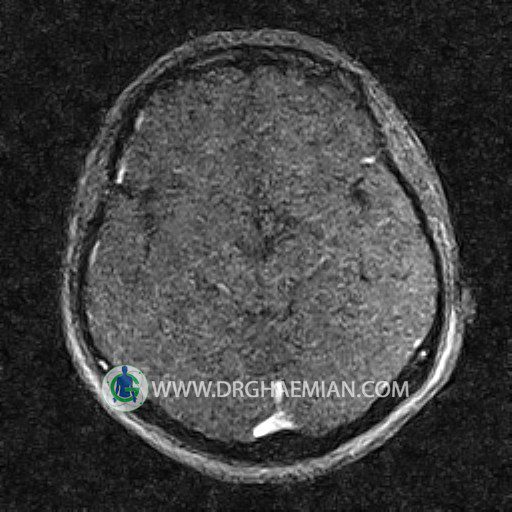

ام آر وی یک روش تصویربرداری دقیق و غیر تهاجمی است که برای معاینه ورید های بدن و ارزیابی سلامت رگ ها استفاده می شود. ورید ها خون را از اعضای بدن به قلب باز می گرداند تا دوباره اکسیژن و مواد مغذی به خون داده شود. ام آر وی جریان خون را ارزیابی و موارد غیرعادی مضر مانند لخته های خونی را شناسایی می کند. در این کیس ترومبوز دیواری مغز در سینوس عرضی راست و ترمبوز جزئی در سینوس عرضی چپ دیده می شود.

Images of the venous cranial vessels demonstrates a superior sagittal sinus of normal caliber with normal arrangement of draining superficial cerebral veins.

The great cerebral vein Galen inferior sagittal , straight sinus and left sigmoid sinus appear normal.

The right sigmoid sinus present a normal caliber.

The other evaluable deep cerebral veins , basal and labbe are normally developed and patent.

The other evaluable portions of the neurocranium show no abnormalities.

– Narrowing of left transverse sinus with filling defect & inthimal irregularity

suggestive for partial thrombosis

– Inthimal irregularity in anterior wall of right transverse sinus suggestive for mural thrombosis

are seen